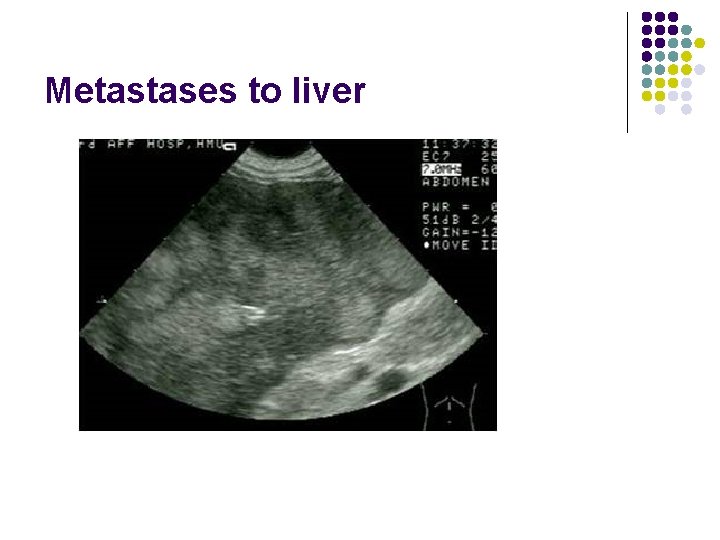

Metastases to liver l l l Organ of origin: colon(42%); stomach(23%); pancreas(21%); breast(14%); lung(13%) Number : multiple(98%); solitary(2%) “Bullseye”:An echogenic center with a surrounding echopenic area Echopenic : Less echogenic than the surrounding liver Echogenic More echogenic than the surrounding liver

Metastases to liver

Metastases to liver